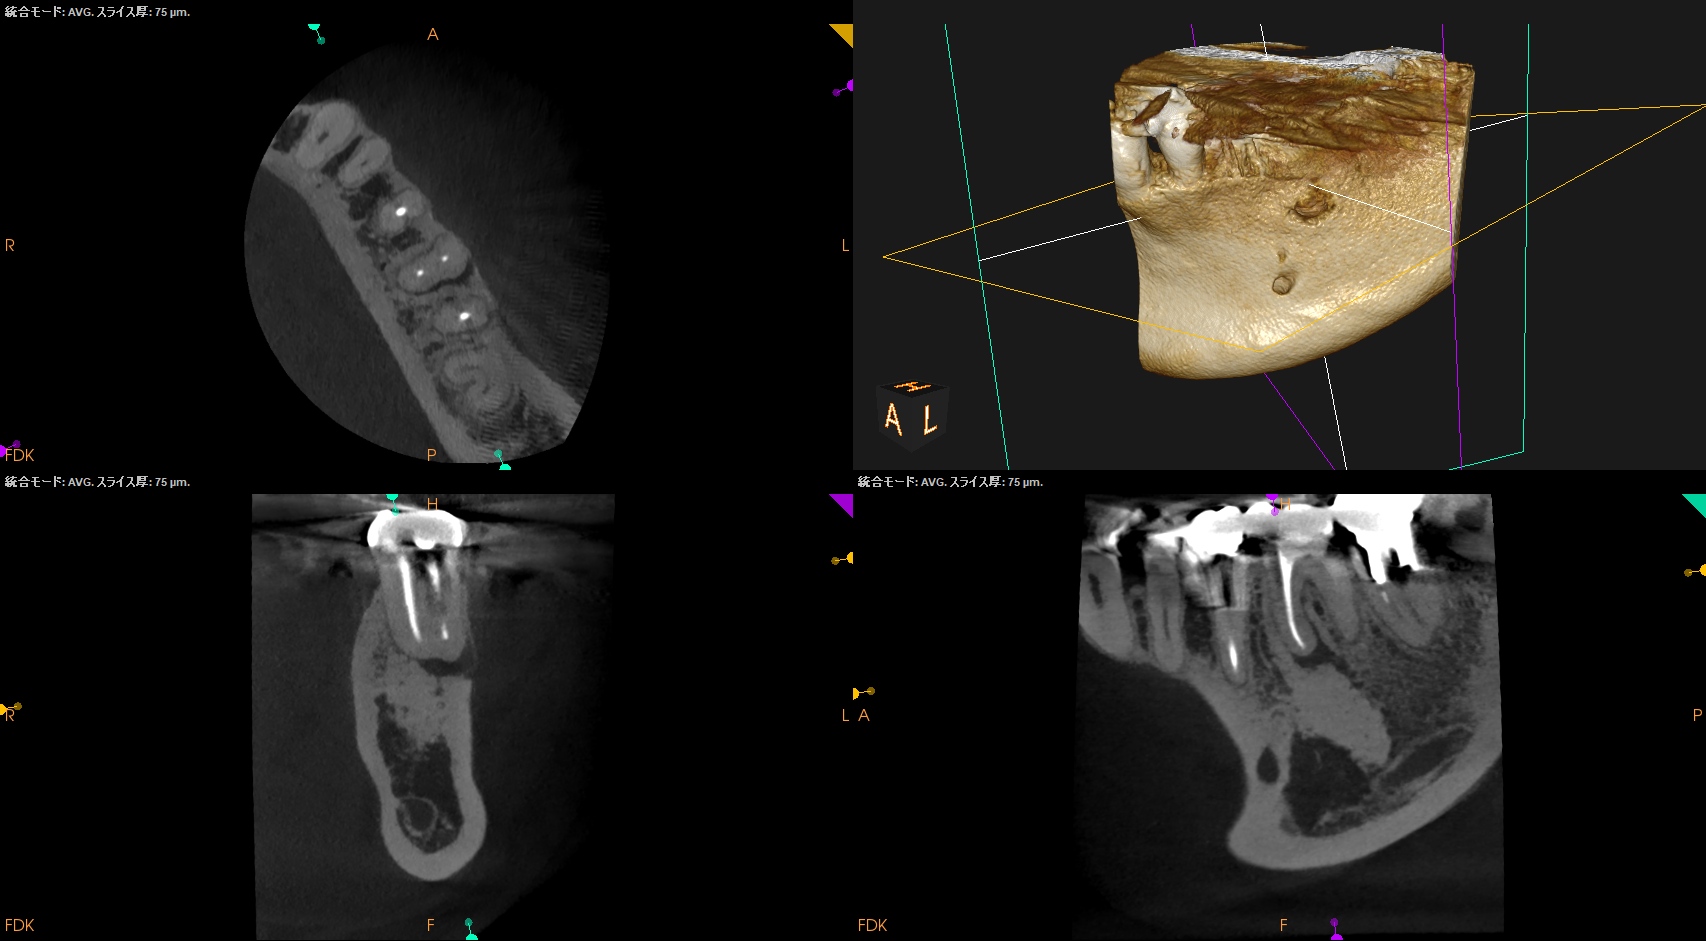

Pre-op CBCT(2025.1.10)

MB

ML

D

根尖病変があるのは近心根のみであるので近心根のみ再根管形成することにした。

MBもMLも穿通させる必要があることがCBCTを見える絵にしていけばわかる。

Pre-op Endo Diagnosis(2025.1.10)

Pulp Dx: Previously treated

Periapical Dx: Asymptomatic apical periodontitis

Recommended Tx: Re-RCT